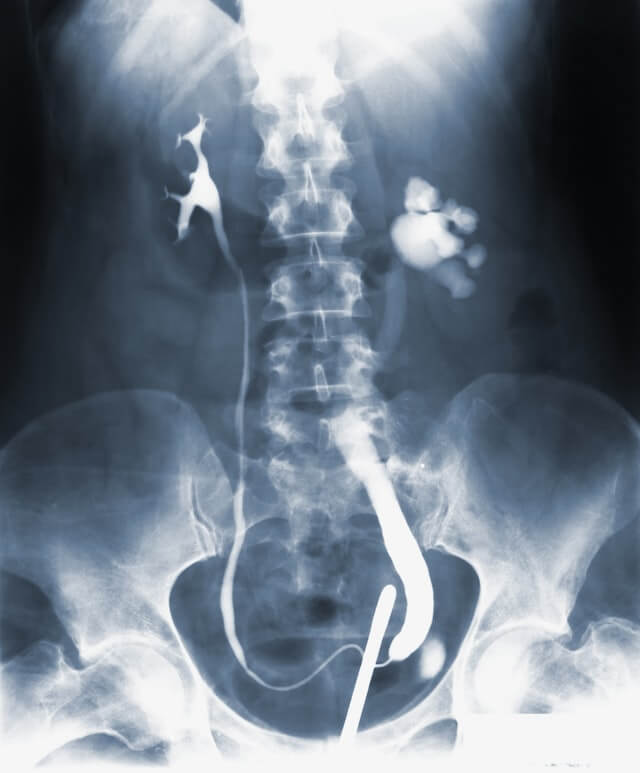

Los cálculos renales, o también conocidos como nefrolitiasis o urolitiasis son formaciones duras formadas principalmente por sales y/o minerales que se acumulan principalmente en los riñones, pero también pueden aparecer en cualquier parte del tracto urinario, como podría ser la vejiga o la uretra.

Estas formaciones también llamadas popularmente piedras en los riñones suelen ser muy dolorosas al irse desplazando en las vías urinarias porque provocan rasgaduras, y en algunos casos infecciones que pueden llegar a causar complicaciones importantes.